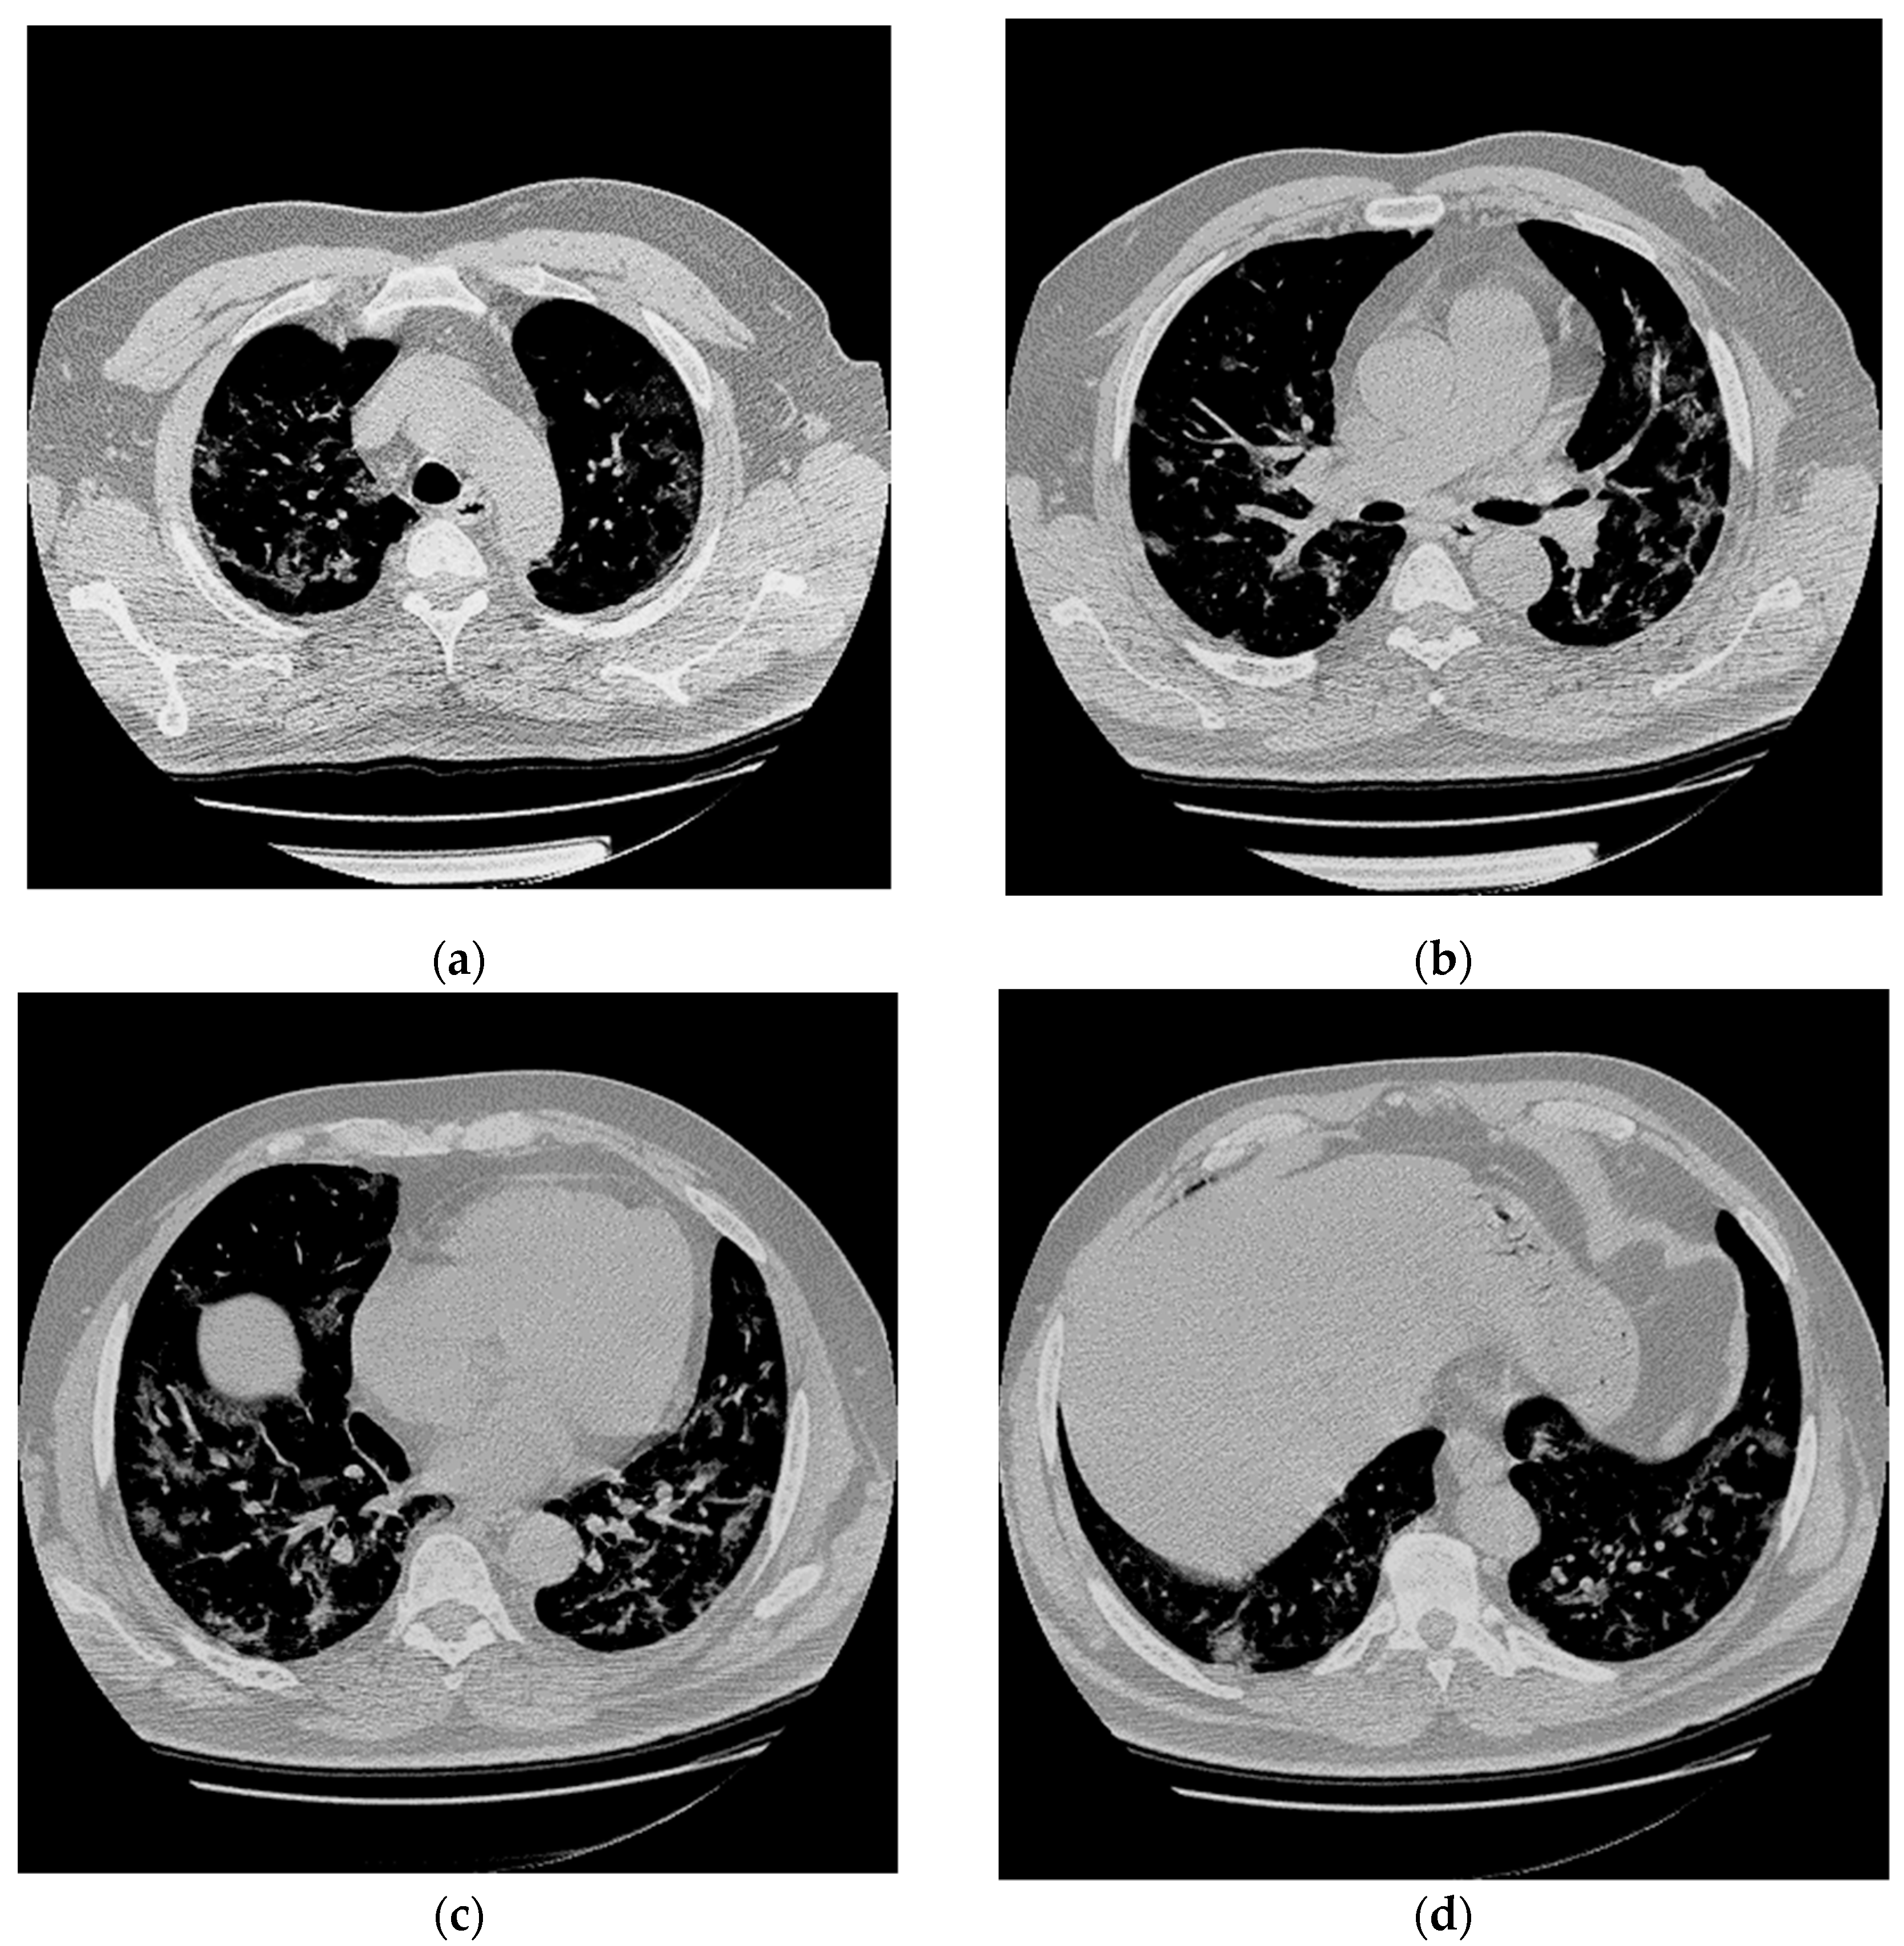

A previously healthy 56-year-old man presented to the hospital with 5 days of fever and dyspnea. Chest Computed Tomography (CT) revealed in all lung lobes multifocal and peripheral areas of interstitial thickening with a “ground glass” appearance due to interstitial pneumonia (Figure 1).

Figure 1.

Chest CT abnormalities in a 56-year-old man with positive RT-PCR test results for SARS-CoV-2. (a–d) Axial nonenhanced chest CT images (lung window) show diffuse bilateral pulmonary ground-glass opacities and dilated segmental and subsegmental vessels.